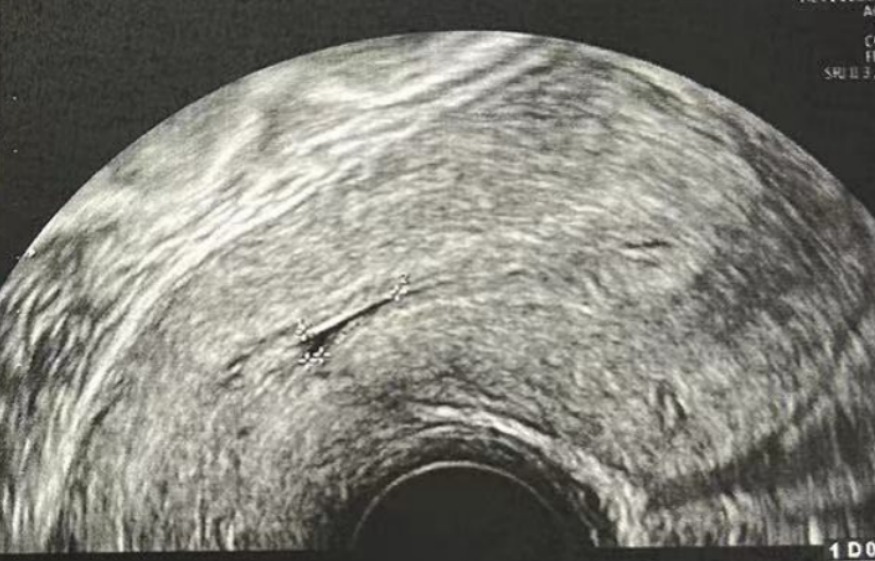

在进行3毫升的子宫峡部切口冲洗后,经过经腹超声检查显示子宫内膜呈三线状,且子宫腔内未见液体。

• Pre-Irrigation灌洗后: